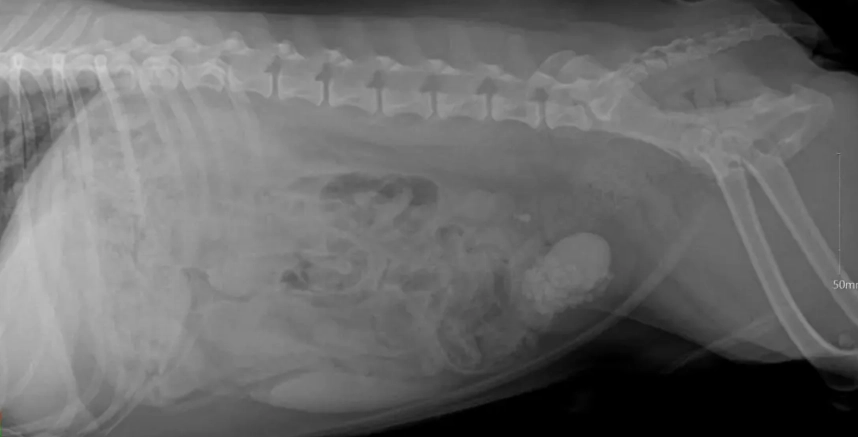

診斷膀胱結石通常需要影像學檢查。X光能顯示鈣化結石,但有些結石(如尿酸結石)在X光下不顯影,這時超音波就派上用場。尿液分析則可檢測pH值、結晶和感染。

獸醫會根據X光、超音波和尿液分析來判斷。如果結石小於5毫米,且狗狗沒有阻塞症狀,可以先嘗試非手術方法。但若結石導致排尿困難、血尿或感染,手術可能是必要選項。